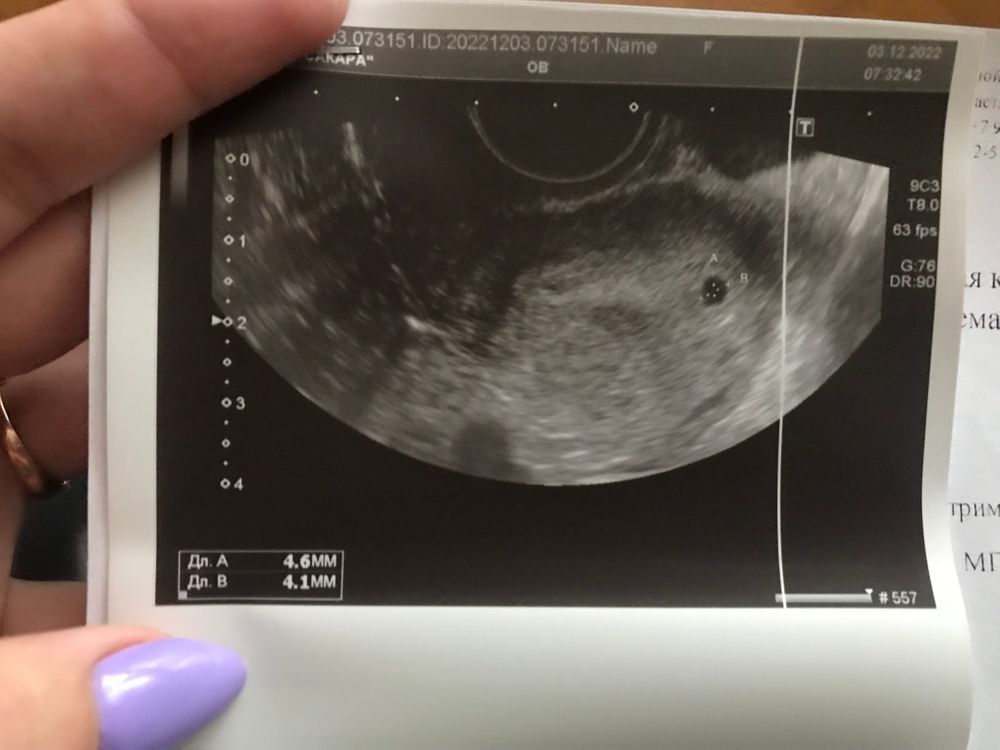

Екатерина, Плодное яйцо 8 мм - 3 недели, а не 5, как Вам написали. При 5 неделях плодное яйцо 21 мм , четко виден эмбрион и желточный мешочек.

Екатерина, у Вас в воскресенье 04.12 только исполнилось по календарю 4 недели, а настоящий размер плодного яйца может быть другим, он может еще не соответствовать строго календарному сроку беременности.